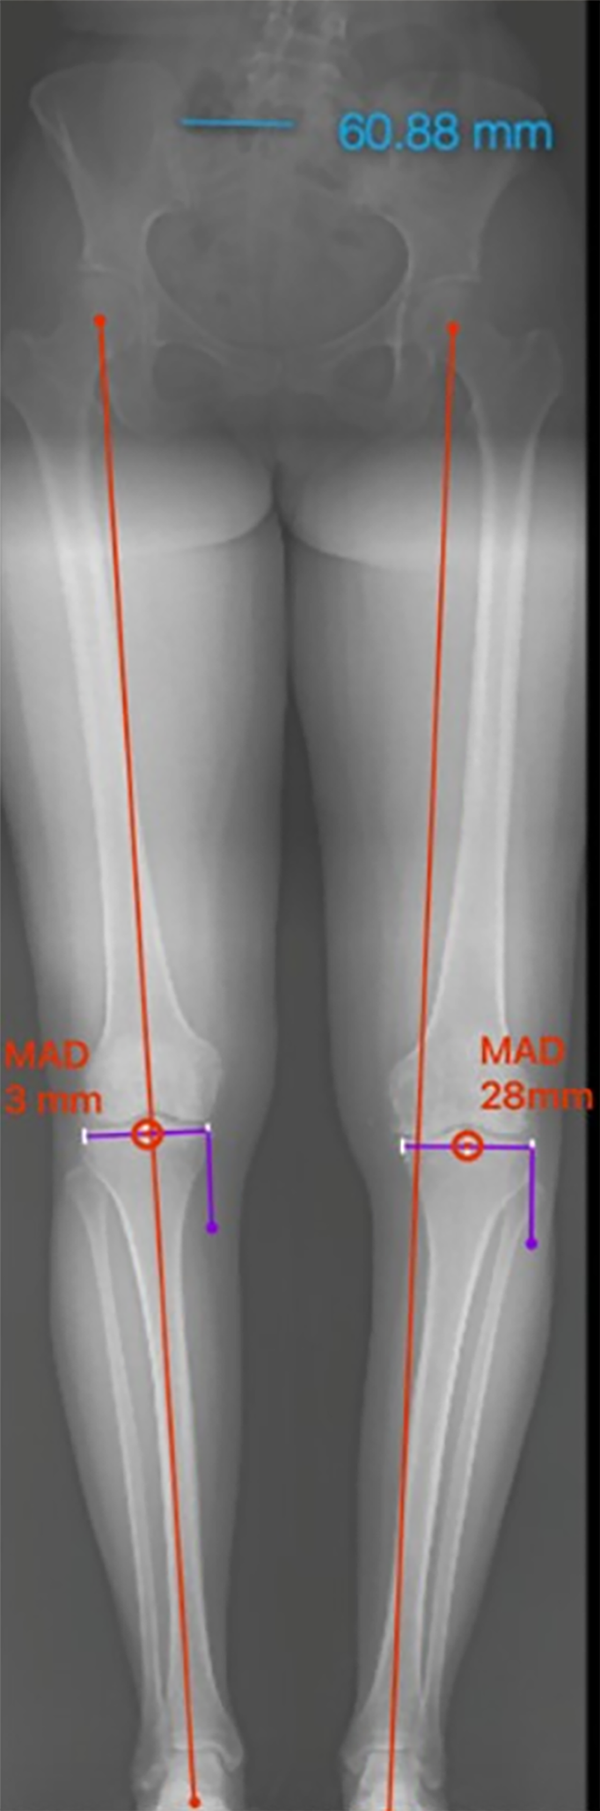

Figura 4: Ángulo femoral distal lateral mecánico (mLFDA): mLDFA y MPTA bilateral, se observa del lado izquierdo una deformidad en varo del fémur 92° (normal 85-90°) y la tibia 84° (normal 85-90°). Lado derecho con una deformidad en varo del fémur 92° y la tibia 87° en valor normal.

Figura 5: JLCA bilateral de 2° (valor normal 0-2°).